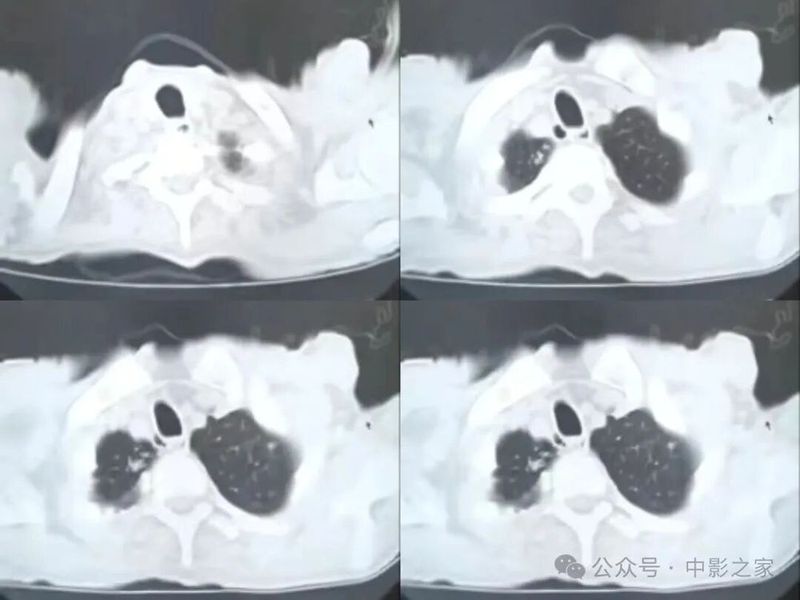

肿瘤患者,肺内病灶抗炎治疗10多天无好转

诊断:肺结核

“烟花征”,为活动性肺结核的CT表现之一。是结核经支气管播散并由多发小叶中央结节堆积而成,形态特征似烟花在空中散开。病理基础为细支气管及肺泡内干酪坏死性肉芽肿。

三、影像表现

1.多形态、多部位

2、天女散花

3、晕征

4、反晕征

5、可伴有空洞